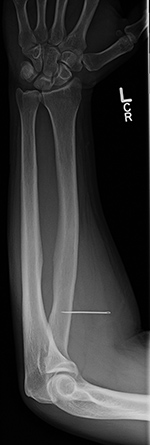

| Frontal and lateral views of the right wrist after placement of a volar T-plate and screws for a comminuted distal radius fracture. On the lateral view there is a retained drill guide (arrow) that was inadvertently left in place. It should have been removed at the end of the surgical procedure. It is not evident on the AP view and was initially overlooked by both an MSK radiologist and the patient's orthopedic surgeon. |